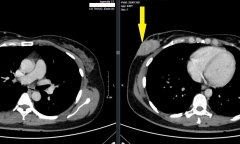

Nam thanh niên mắc cơn bão giáp trạng dẫn đến suy tim, phù phổi, xơ gan, rung nhĩ. Căn bệnh khá hiếm gặp nhưng vô cùng nguy hiểm.